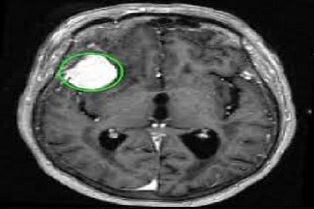

Ms. Roshan Jahan, from the Department of Computer Science & Engineering, Integral, simplifies that the algorithm is able to identify a tumor at a very early stage also. There are six classes of images used for machine learning :

• Class 1: There is no brain tumor.

• Class 2: There is a brain tumor in the lower right part of the brain.

• Class 3: There is a brain tumor in the lower left part of the brain.

• Class 4: There is a brain tumor in the lower center part of the brain.

• Class 5: There is a brain tumor in the higher right part of the brain.

• Class 6: There is more than one brain tumor in different places of the brain.

Integral Research asserts that a regress testing has been done to test the reliability of an algorithm and found it 92.17% efficient. After training of algorithm with the dataset, it was implemented on the Raspberry Pi 3. The Raspberry Pi is a small computer that does not work as fast as a laptop but fully functioning and can be used for various applications. The team has implemented the algorithm on the Pi so that it can be used in real time application by connecting the Pi to an fMRI machine. The algorithm on the Pi would then immediately classify the images and say if a brain tumor is present.